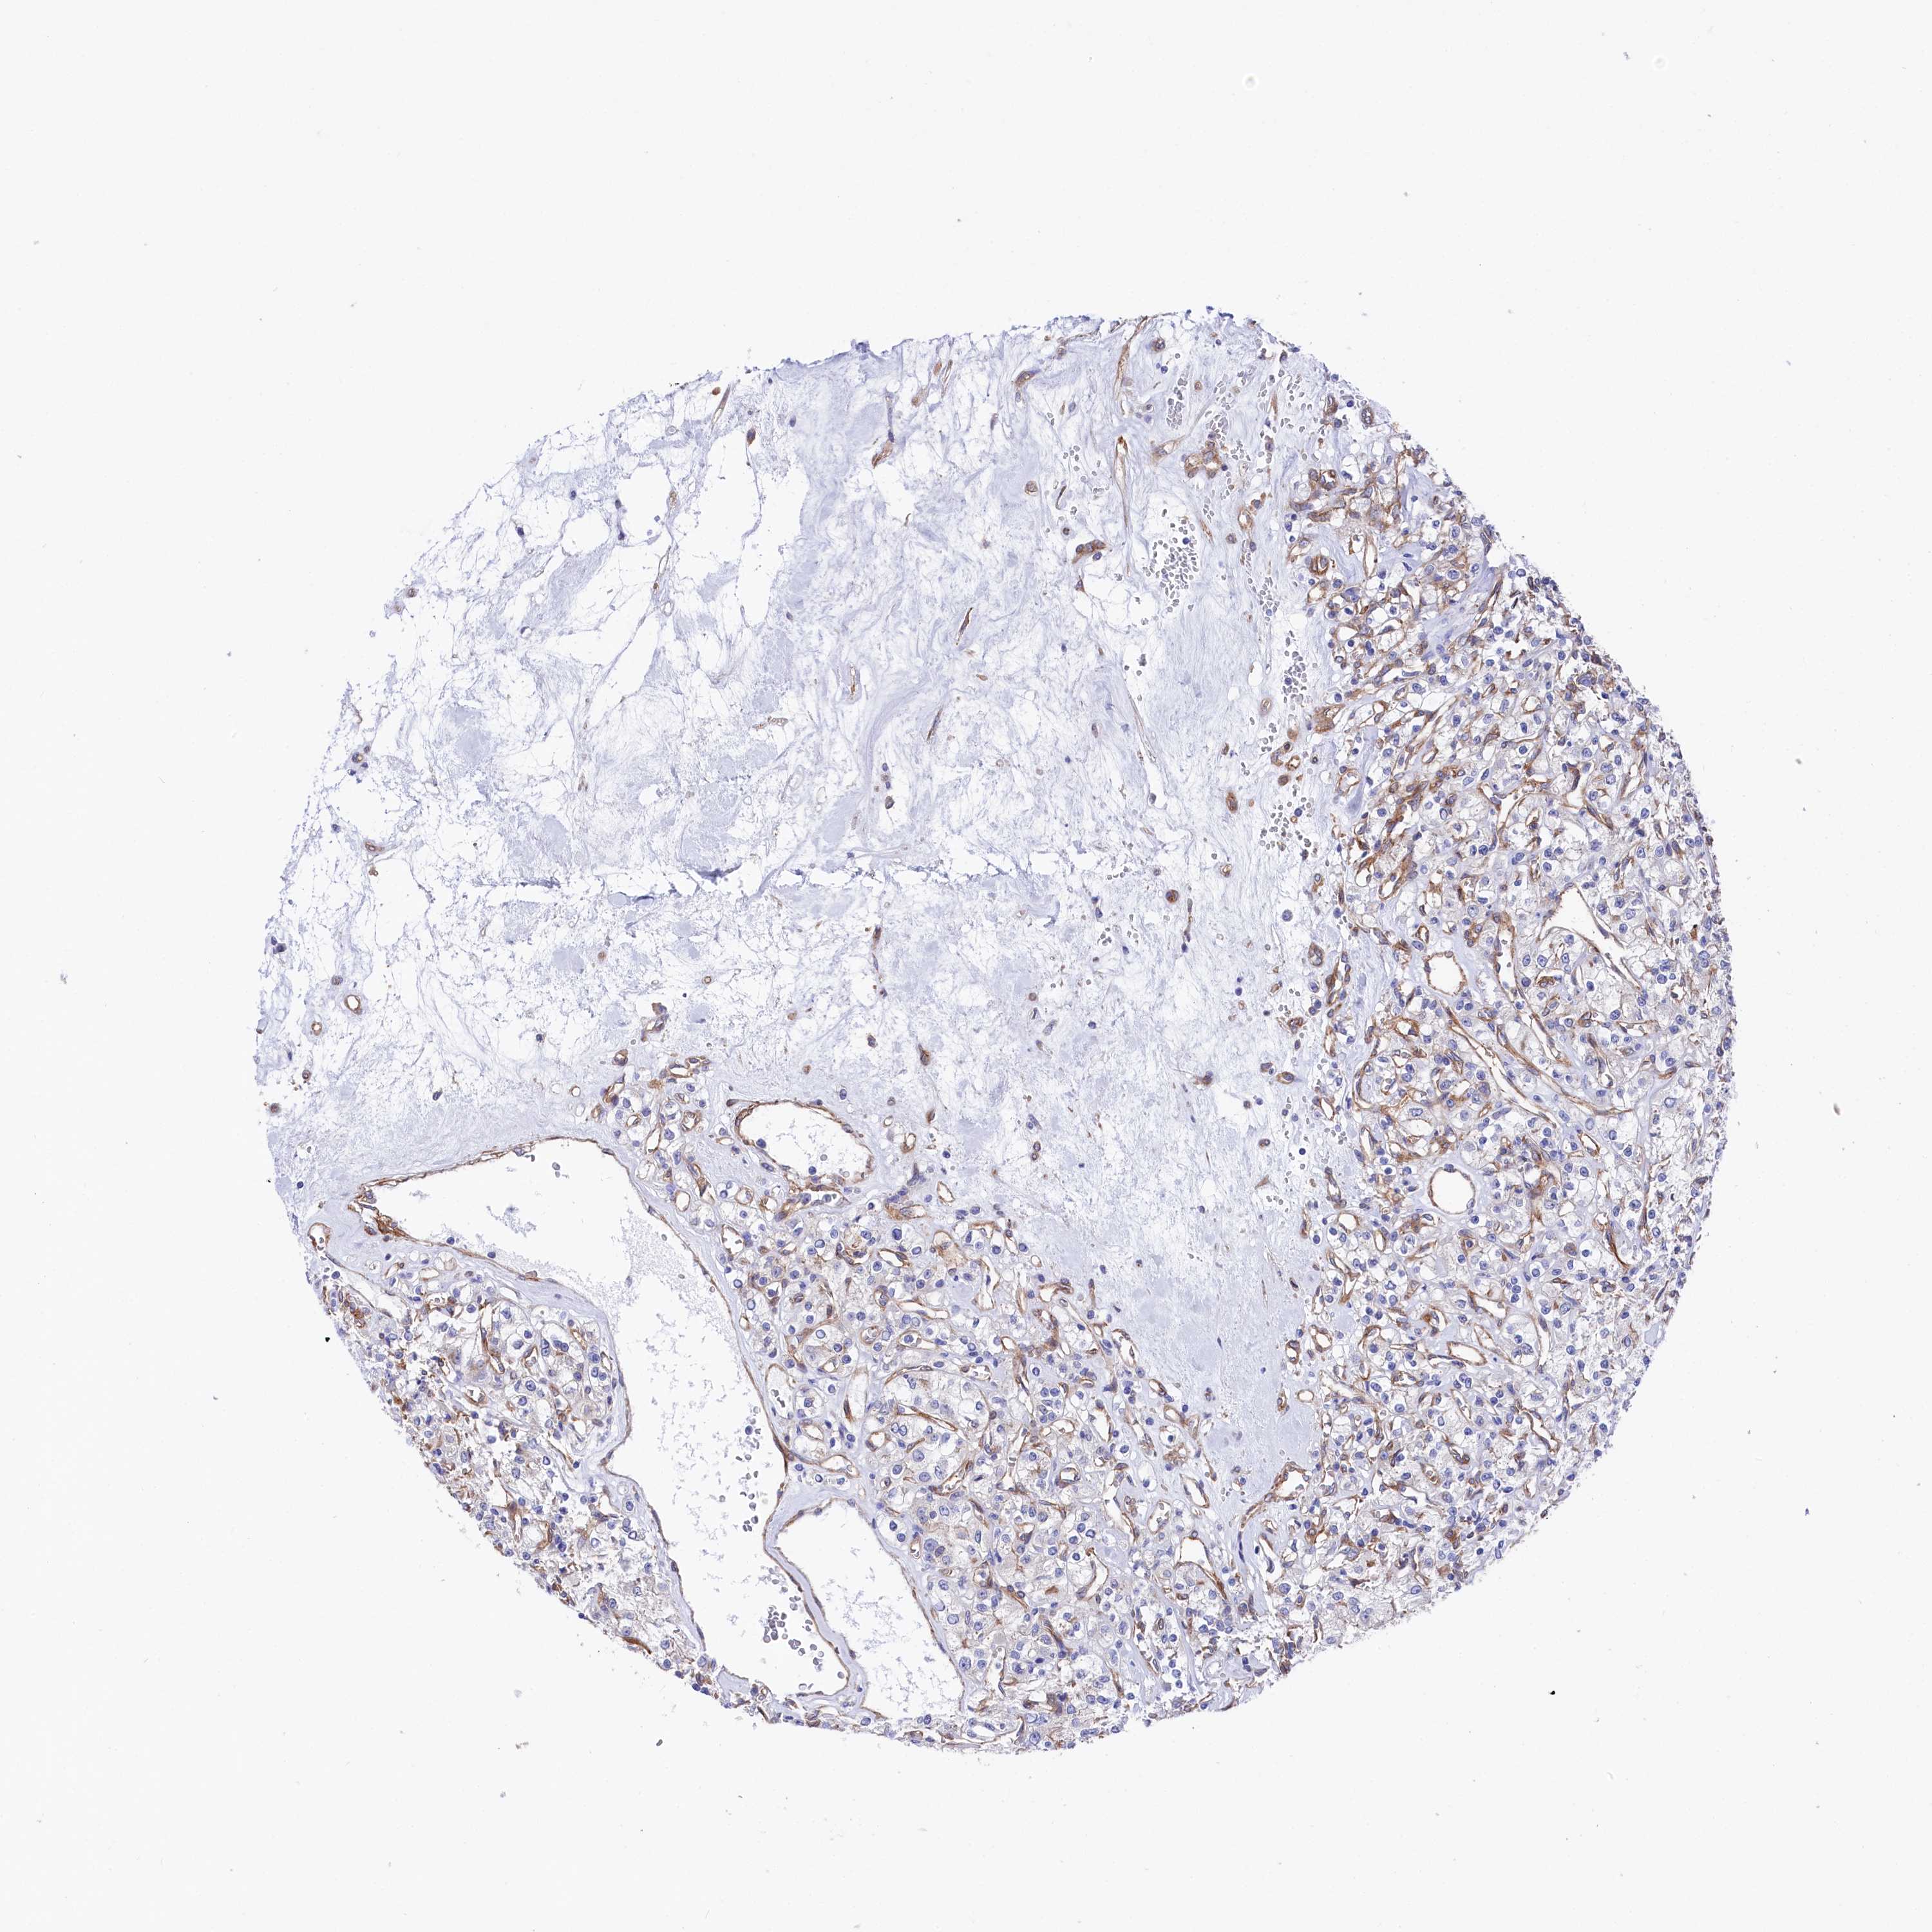

KIDNEY RENAL PAPILLARY CELL CARCINOMA (TCGA) - Interactive survival scatter ploti

The Survival Scatter plot shows the clinical status (i.e. dead or alive) for all individuals in the patient cohort, based on the same data that underlies the corresponding Kaplan-Meier plots. Patients that are alive at last time for follow-up are shown in blue and patients who have died during the study are shown in red.

The x-axis shows the expression levels (FPKM) of the investigated gene in the tumor tissue at the time of diagnosis. The y-axis shows the follow-up time after diagnosis (years). Both axes are complimented with kernel density curves demonstrating the data density over the axes. The top density plot shows the expression levels (FPKM) distribution among dead (red) and alive patients (blue). The right density plot shows the data density of the survived years of dead patients with high and low expression levels respectively, stratified using the cutoff indicated by the vertical dashed line through the Survival Scatter plot. This cutoff is automatically defined based on the FPKM cutoff that minimizes the p-score. The cutoff can be changed by dragging the vertical line or by entering a cutoff value in the square labeled "Current cut-off".

Under the Survival Scatter plot the p-score landscape (black curve; left axis) is shown together with dead median separation (red curve; right axis). Dead median separation is the difference in median mRNA expression between patients who have died with high and low expression, respectively. It is calculated as follows: median FPKM expression of dead patients with high expression - median FPKM expression of dead patients with low expression. This is intended to aid the user in visually exploring custom cutoffs and the associated p-scores and dead median separation.

Individual patient data is displayed and can be filtered by clicking on one or more of the category buttons on the top of the page. Categories describing expression level and patient information include: high, low, alive, dead, female, male and tumor stages. The scale of the x-axis can be toggled between linear and log-scale by clicking on the "x log" button. Mouse-over function shows TCGA ID, patient information and mRNA expression (FPKM) for each patient.

& Survival analysisi

Kaplan-Meier plots summarize results from analysis of correlation between mRNA expression level and patient survival. Patients were divided based on level of expression into one of the two groups "low" (under cut off) or "high" (over cut off). X-axis shows time for survival (years) and y-axis shows the probability of survival, where 1.0 corresponds to 100 percent.

TNKS1BP1 is not prognostic in Kidney Renal Papillary Cell Carcinoma (TCGA)